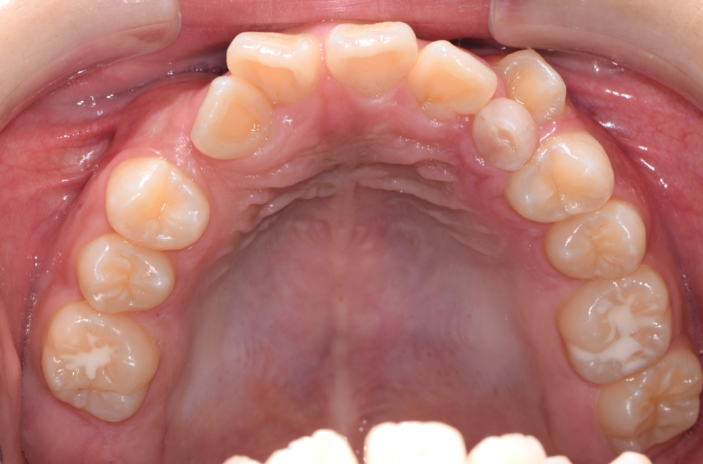

早期牙弓擴張術 (Rapid Maxillary Expansion)

牙弓擴張主要針對上顎進利矯正,透過牙弓矯正裝置裝進上顎牙齒內側,以嘗試撐開上顎的牙弓、擴張空間,慢慢地利用裝置的壓力來把牙弓擴張,讓整個上顎變大,並讓上顎能容納更多牙齒,藉此使牙齒排列回復正常。

上牙弓正常情況下會比下牙弓大,因此在正常咬合的狀態,上顎的牙齒應全都包覆在下顎牙齒的外側。但因基因遺傳、日常生活的壞習慣、因鼻塞長期習慣用口腔呼吸導致很多人牙弓越來越小,導致口腔沒有足夠的空間容納牙齒,因此造成齒列不整、上顎發育不佳,更可能有戽斗狀況產生。

上顎擴弓後